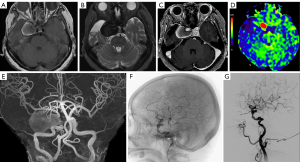

At the time of the current presentation, the patient underwent head CT, computed tomography angiography (CTA), magnetic resonance imaging (MRI), and time-of-flight magnetic resonance angiography (TOF-MRA). CT showed a low-density lesion in the right cavernous sinus, with a clear boundary, a flocculent high-density shadow inside, and ring calcification at the edge (Figure 1A). The CT color map showed the lesion more intuitively than non-enhanced CT image (Figure 1B). CTA showed multiple nodulous protrusions in the lesions, communicating with the cavernous segment of the right internal carotid artery (ICA) (Figure 1C). In addition, two other small aneurysms were observed in the right ICA (Figure 1D).